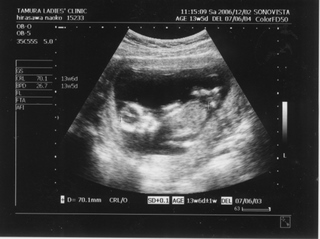

5ヶ月(18週と5日) 体重:262g BPD(頭を上から見た耳から耳の幅のような感じ):46.8㎜ FTA(お腹の断面):15.9平方㎝ FL(大腿骨長 太ももの骨の長さ):22.7㎜ 6ヶ月(22週と5日) 体重:602g BPD(児頭大横径 頭を上から見た耳から耳の幅のような感じ):57.6㎜ FTA(体幹横断面 お腹の断面):26.6平方㎝ FL(大腿骨長 太ももの骨の長さ):38.1㎜ まだこの頃は顔と上半身が収まっていました。 検診は妊娠23週までは、4週に一度なのでドキドキとワクワクです。 ちゃんと成長してるかなあなんて考えて行って、 心音をきいたり、エコーを見て毎回安心と喜びがわいてきます(*^_^*) たった4週で、体重は3倍近くにも!かわいいなあ☆ 6ヶ月の検診日ダンナっちは仕事だったから、 エコー写真を携帯で撮って送ると、 『目ん玉でてない!?』 と返事が返ってきました。 眼球がそう見えるんだろうけど、目のとても細いダンナっちには 衝撃的だったんですね(^。^;) 胎動を初めて感じた日をわたしはわかりません・・・ メモにとるなり、日記にかくなりすることをすっかり忘れてしまって、 今となって後悔<<o(>_<)o>> ダメな母親めっ と思いつつも、わたしらしいと感じ笑っています(^_^;) 12月の末に友達に、 「腸の動きか!?って思うのはあるんだけどまだよくわかんない」 と言ったのを覚えているので、12月の終わりから1月にかけての あたりなんでしょうね。 いつの間にかポッコポッコしていました! ベイビーこんなママだけどよろしく└|∵|┐♪┌|∵|┘ 6ヶ月までは、普通にそれまで履いていたジーンズも入っていたんだけど、 6ヶ月終わるころには、急に入らなくなってビックリしました~ 食生活の変化も特になかったです。 あ、ポテトチップスあまり自分で 買わなかったのに、1週間くらいブームの時期がありました!妊娠による影響かな!? 今、ベイビーはしゃっくりをしているみたいです |